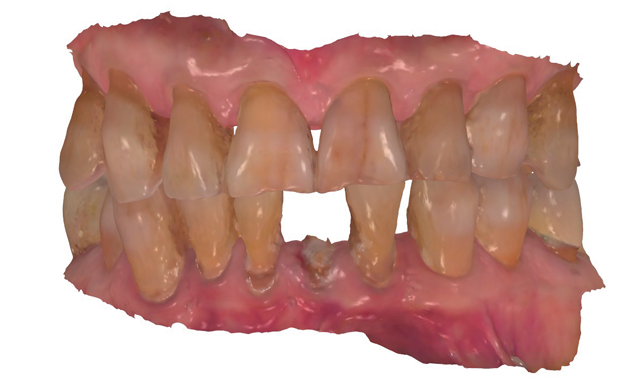

Fig. 1

An 88-year-old man presented for restoration of tooth #25, which was fractured and had been endodontically treated (Fig. 1). A thorough intraoral and radiographic examination was performed, which revealed damage to the remaining anterior mandibular teeth incurred over the years as a result of scaling and curettage (Fig. 2). This damage to the

Fig. 2

root surface of the lower incisors-which was visible on the radiograph (Fig. 3)-is known as “Riffle-ization.” Described by Dr. Riffle as a technique for removing every last bit of calculus during repeated root scaling, what is now known as “Riffle-izing," ultimately-over the years-changes the shape of the neck of the tooth to resemble an hour glass.

Therefore, based on the clinical and visual evaluation, the preferred treatment would be to restore the fractured #25 with a post and crown and four splinted crowns to restore the anatomy of the four incisors and increase their resistance to both mobility and fracture.

In the past, the splinted crowns required for this case had to be constructed with porcelain-fused-to-metal (PFM).9 Today, the use of zirconia allows for a stronger, more esthetic fixed construction.10 Therefore, after analyzing all of the case information, it was decided with the patient that the final treatment would consist of splinted monolithic zirconia (Zenostar/Wieland, Ivoclar Vivadent) crown restorations.